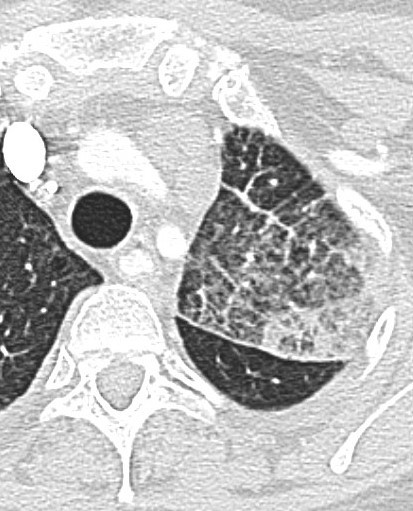

Lung Azygous fissue

Accessory fissure present in less than 1% of patients, seen in the presence of an azygous lobe. An azygous lobe is an anatomic varian where the right upper lobe apical or posterior segments are encased in their own parietal and visceral pleura.